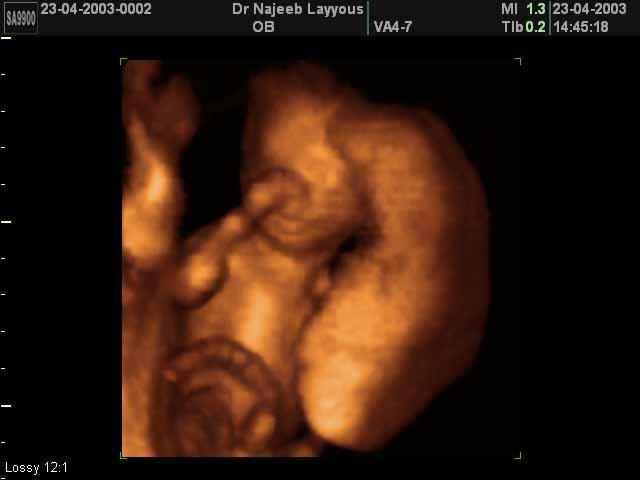

- 3D Fetal Profile Ultrasound Scan Photos

3D Second Trimester Ultrasound Scan Photos-second part of pregnancy | Dr N Layyous